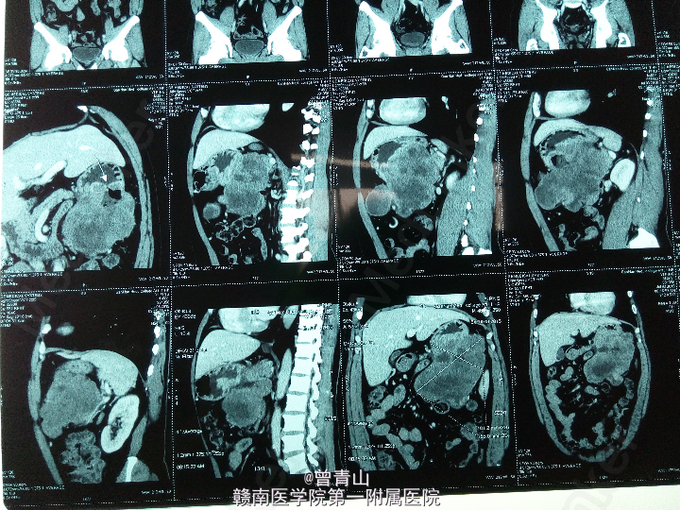

查体:腹部膨隆,软,全腹无压痛及反跳痛,左中下腹可及一大小约16.1*9.3cm的硬性肿块,活动度差,与周围组织分界不清,肝脾肋下未触及,移动性浊音阴性,肠鸣音减弱。全腹部增强CT提示:左上腹部可见一大小约10.1*15.5cm分叶状软组织肿块影,边界清楚,密度不均,增强扫描肿块不均性强化,中央可见片状无强化坏死区;肿块与胃体大弯侧关系密切,并与胃穿通,肿块内可见气液平面。电子胃镜提示:胃体占位。取活检并送病检提示:胃间质瘤。血分析:白细胞(仪器法)9.55*10^9/L,红细胞(仪器法)3.4*10^12/L。肝功能:总蛋白(双缩脲法)62.9g/L,白蛋白(溴甲酚绿法)37.2g/L,空腹血糖(酶法)7.96mmol/l。